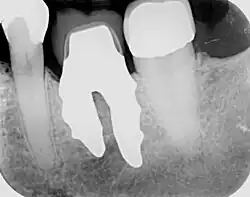

RAIs are custom made to perfectly fit the tooth socket of a specific patient immediately after tooth extraction. Therefore every implant is unique. As an optimised root-form it is much more than a simple 1:1 replica of a tooth. Since it exactly fills the gap left after the tooth is extracted, surgery is rarely needed. The implant can be produced from a copy of the extracted tooth, an impression of the tooth socket, or from a CT scan or CBCT scan.[7] The advantage of a CBCT scan is that the implant can be produced before extraction. With the former methods, it takes one or two days to fabricate an implant.

- Obtain the 3D form of the tooth to be replaced. This is done either through careful tooth extraction and scanning of the root, taking an impression of the tooth socket, or a pre-op CBCT scan. The root analogue implant is produced using modern CAD/CAM technology, based on the principle of differentiated osseointegration;

- Placement of the root analogue implant by tapping it in. In general, no surgery is necessary. In particular, no sinus lift or invasive surgery is ever necessary. The implant is placed immediately if it has been produced beforehand from a CBCT scan, or the next day if root has to be scanned or an impression of the socket is used. A protective splint is fitted to protect the implant during the healing period.

- Natural form: a custom milled anatomic implant replicates the natural form of a tooth, so it simply fits into the tooth socket. Like the original tooth, a root analogue implant can have single- and multi-rooted forms.